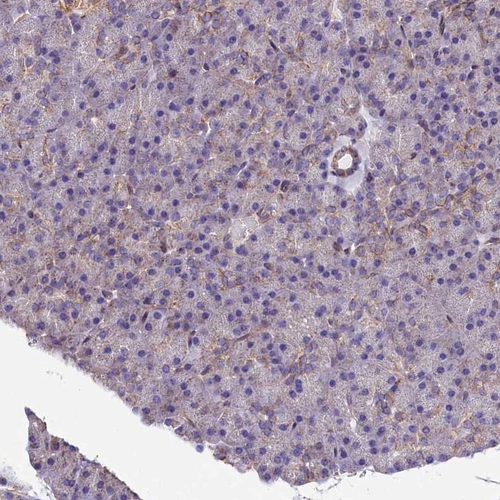

Immunohistochemistry analysis in human fallopian tube and pancreas tissues using Anti-ATP2B4 antibody. Corresponding ATP2B4 RNA-seq data are presented for the same tissues.